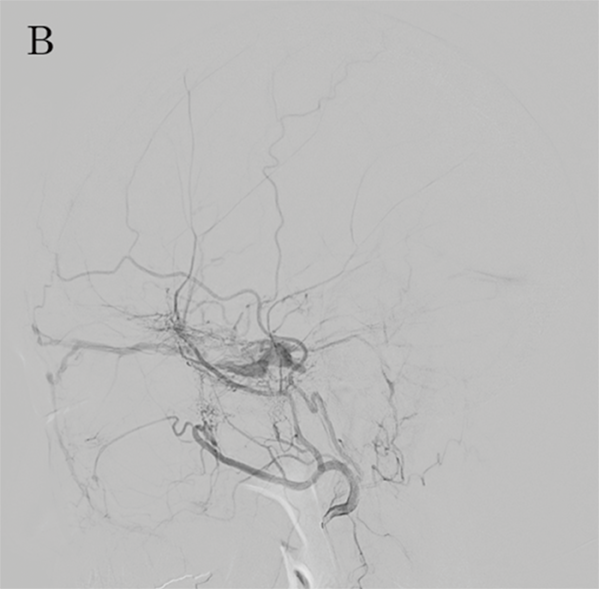

Перед проведенням трансвенозної та трансартеріальної емболізації CSdAVF за допомогою суперселективної шунтової оклюзії (SSSO)2 важливо визначити точку шунта на передопераційних зображеннях DSA (малюнок 8A та 8B).

Однак зображення DSA потрібно перевіряти багато разів.

Малюнок 8A: DSA CSdAVF, вид спереду 1

Малюнок 8B: ADSA CSdAVF, вид збоку.